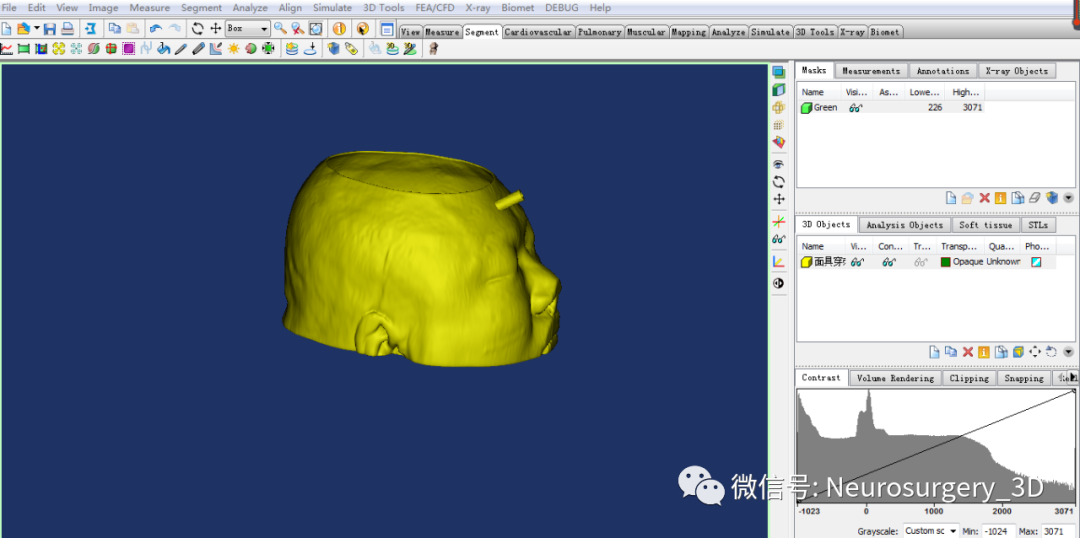

9、把生成穿刺导板面具的STL导入到Mimics软件中,应用Simulate剪切成规则需要模型。

10、把通过Mimics剪切后的穿刺导板再以STL格式保存到桌面上。

11、穿刺导板镂空:把Mimics剪切后的导板导入E3D软件界面,进行镂空处理后备用。